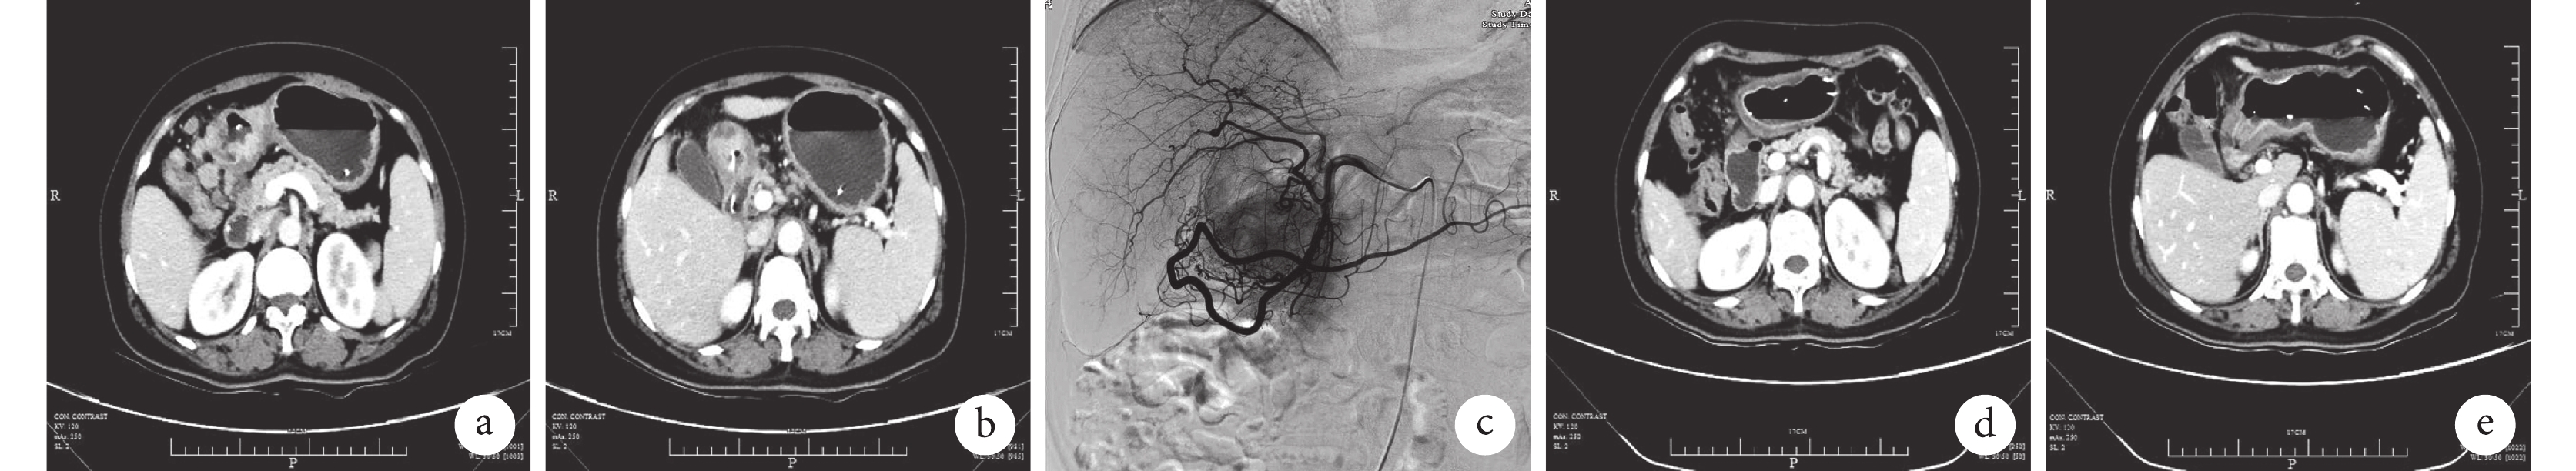

示病例 6 治療前后的影像圖

a、b:轉化治療前增強 CT 發現該患者腫瘤侵犯十二指腸球降部,幽門下及肝十二指腸韌帶多發淋巴結腫大、融合并包繞主要血管;c:經胃網膜右動脈行腫瘤血管造影后 TACE 治療;d、e:轉化治療后的增強 CT 圖像見降期明顯

轉化治療前常規進行血液學及心肺功能檢查,進行全身狀態及營養狀態評估,常規進行胃鏡檢查評估病變的部位、長徑、鏡下病變的大體分型。常規進行胸腹部增強 CT 檢查(圖 1a、1b)以實施術前臨床分期評估,存在胃外可疑病灶時進行 PET-CT 檢查,排除遠處轉移。

患者在入院后常規進行營養狀態評估,必要時給予輸血及腸內營養支持治療。SATA 轉化治療方案如下。① 于第 1 天和第 30 天行 TACE 治療:患者仰臥于手術臺上,2% 利多卡因局部麻醉后行右側股動脈 Seldinger 穿刺法成功后置入 5F 導管鞘,經鞘引入 5F-RH 導管插管至腹腔動脈造影,根據腫瘤部位超選腹腔干(皮革胃)或胃網膜右動脈(病變位于胃下1/3處)或胃左動脈(病變位于中上2/3區),經動脈灌注奧沙利鉑(80 mg/m2)及依托泊苷(80 mg/m2),再推注適量明膠海綿顆粒(350~560 μm)行腫瘤滋養血管栓塞(圖 1c)。② 替吉奧第 1~14 天口服,3 周為 1 個療程(體表面積<1.25 m2時,40 mg,2 次/d;1.25 m2≤體表面積<1.50 m2時,50 mg,2 次/d;體表面積≥1.50 m2,60 mg,2 次/d)。③ 甲磺酸阿帕替尼 0.5 g 第 1~58 天口服,1 次/d。轉化治療 4 周后再次行影像學檢查,評估轉化治療效果。

轉化治療后行腹部增強 CT 評估(圖 1d、1e)是否具備手術指征,對有手術指征的患者常規進行腹腔鏡探查。手術由同一組手術醫師完成,標準術式根據病灶口側緣至齒狀線的距離選擇開腹手術或腹腔鏡輔助根治性遠端胃或全胃切除術聯合 D2/D2+區域淋巴結清掃術。標準的消化道重建方法為遠端胃切除后采用殘胃空腸 Roux-en-Y 吻合、全胃切除后行食管空腸 Roux-en-Y 吻合。